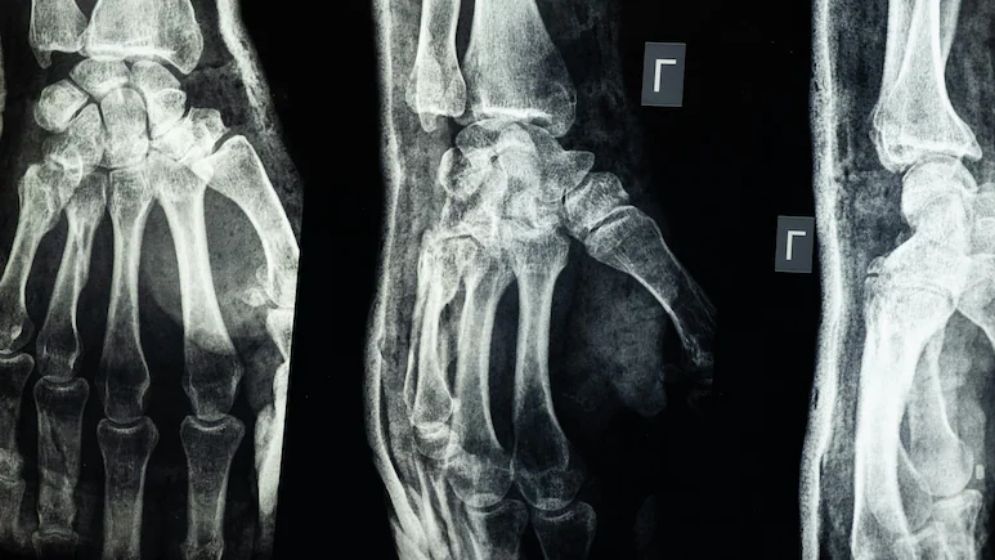

Researchers in China claim to have developed a medical adhesive capable of joining broken bones in just three minutes. This new “bone glue” can not only fuse fractured bones but also stabilize the broken fragments, and it naturally absorbs into the body once the bone has healed. This eliminates the need for a second surgery to remove implants.